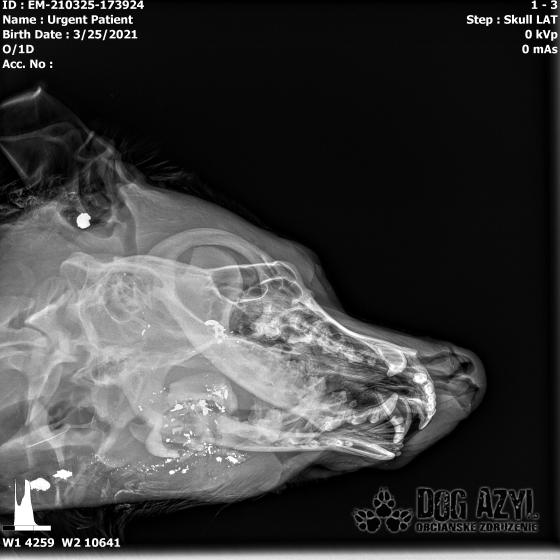

Ona ležala na ľavo, on na pravo od zavesenej šunky, ktorá mala zrejme slúžiť ako návnada, aby sa terče nehýbali.. Uprostred ničoho, bez svedkov, bez dôkazov... Pár kvapiek krvi na ceste.. Ona to schytala jedinou ranou do srdca.. On má roztrieštenú sánku, schytal to do hlavy..

/Strašne to chcem dopísať tak, aby to bolo čitateľné a pochopiteľné, ale celá sa klepem od zlosti a nevidím cez slzy.../ Lebo Ona už meno nikdy nebude mať.. On dostal meno Baris a bojuje o život!!! Má dolámanú sánku a je v šoku!!! Dostal prvú pomoc, analgetiká a priorita bola znížiť jeho teplotu z 41,4°C!!!

Ústami nevie pohnúť, jazyk si nevie ovládať a tak sa sám nedokáže schladiť ani napiť. Podľa RTG sú srdiečko a pľúca v poriadku, ale vôbec nemá vyhraté!!! Niekto chcel Barisa zlikvidovať, ale my za neho budeme bojovať do posledného dychu!!! Zajtra bude prevezený na veterinárnu kliniku Sibra centrum, kde ho čaká team špecialistov z oblasti chirurgie, neurológie a ortopédie. Ak je čo i len najmenšia nádej, že Baris bude môcť žiť, tak BARIS BUDE ŽIŤ!!!